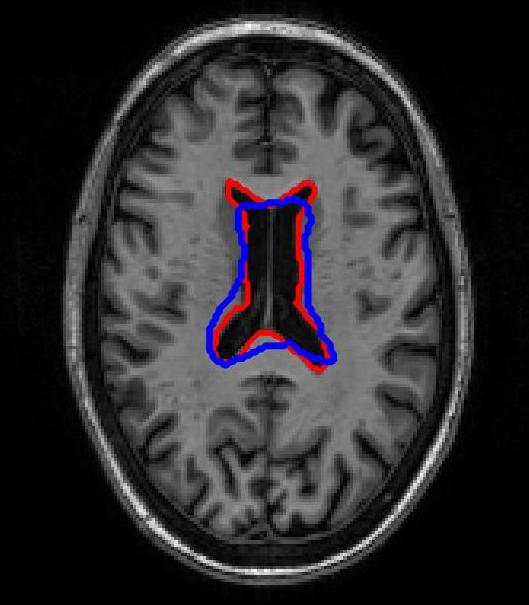

FigureΒ 3 shows results for brain image registration. We show the reference image in FigureΒ 3 (a) followed by an example floating image in FigureΒ 3 (b). The ventricle structure to be aligned is shown in red in both images. FigureΒ 3 (c)-(e) shows the deformed structures obtained by applying the registration field obtained from different methods to the floating image and superimposing these structures on the atlas image. The deformed structures from the floating image are shown in blue. In case of perfect registration the blue and red contours should coincide. In this case SR-Net actually does better than VoxelMorph, while SR-Net does significantly worse due to absence of segmentation information.